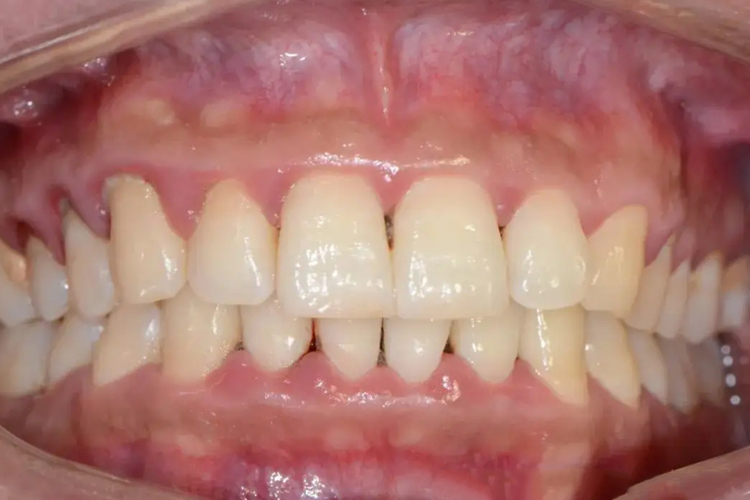

牙槽骨是上下颌骨包围和支持牙根的突起部分,骨质较疏松,且富于弹性,是支持牙的重要组织。容纳牙根的窝称牙槽窝,在冠方的牙槽窝的游离端称牙槽嵴。牙槽嵴的形态在前牙区为圆柱状,磨牙区为扁平状,而在颊舌侧变薄甚至消失。牙槽骨从X线片中,可以观察到邻间牙槽骨的高度和外形。